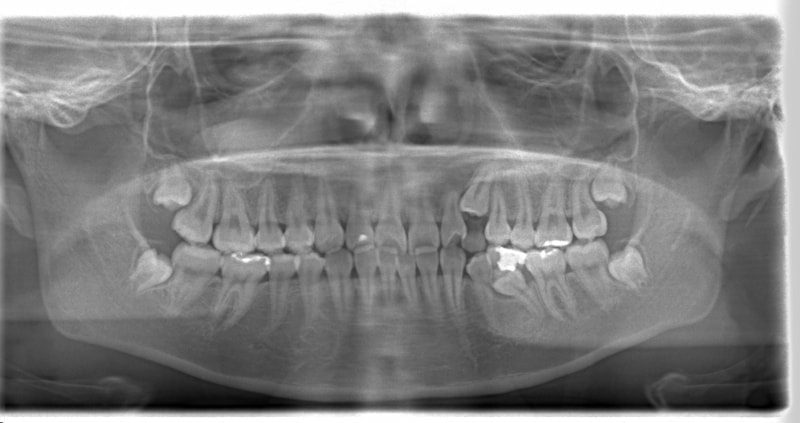

左上3番左下5番埋伏歯

治療法:フルパッシブブラケット:T21

治療前